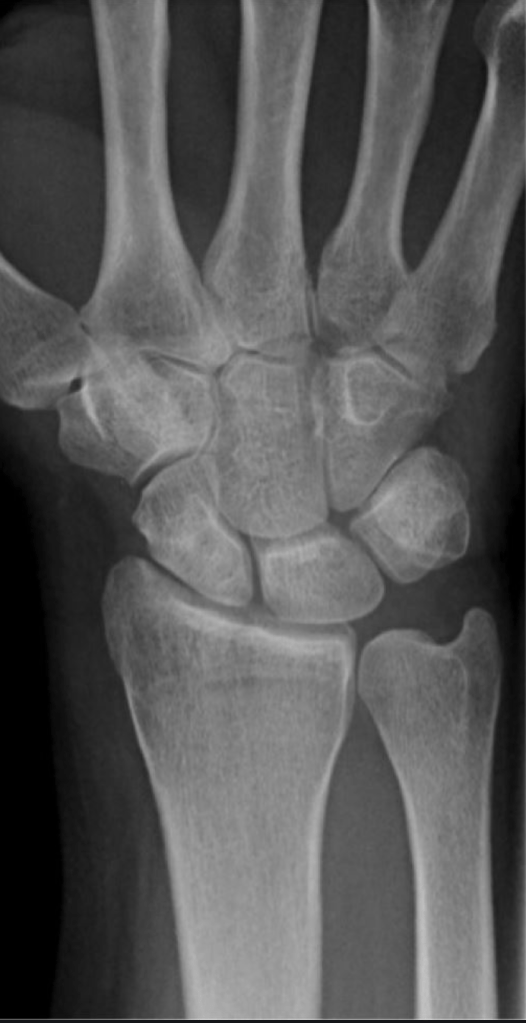

It is actually difficult to determine what will be the natural history of Kienbock’s disease in patients who first present. The condition is sometimes diagnosed very early on, before any xray changes are seen. In other patients the condition presents when the lunate bone fractures or breaks because of bone death.

Kienbock’s disease can be classified according to the changes seen on xrays and scans, and we try to classify the condition in all patients, so that we can give an idea of what is likely to happen. If, for example, a patient presents with stage 2 Kienbock’s, but 6 months later has progressed to stage 3, then we assume that the disease process is active. If no progression of the condition is seen on serial xrays, then we can say that the disease process is static.